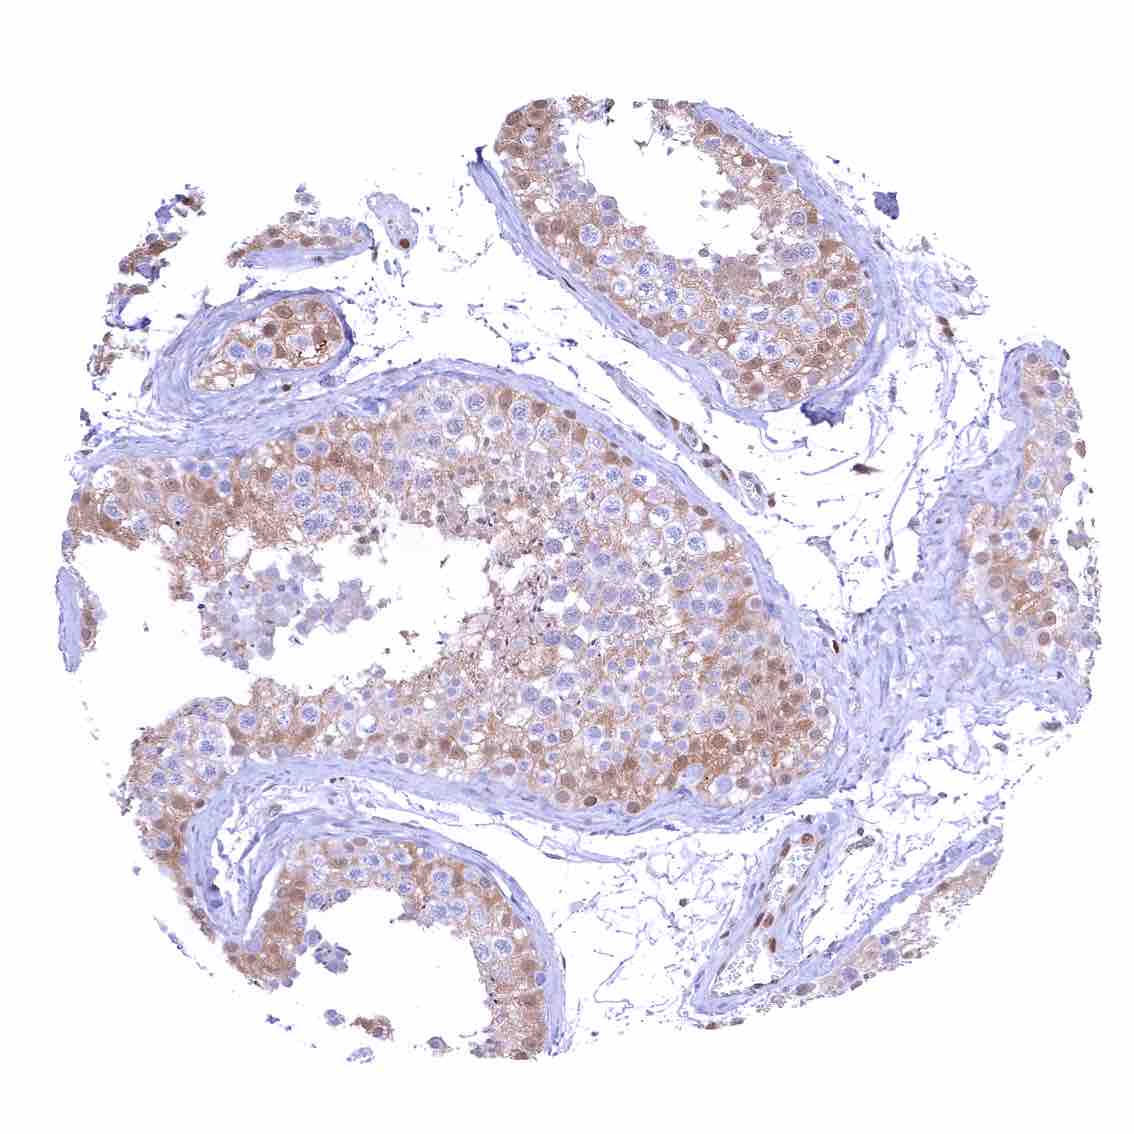

Testis – Weak to moderate nuclear p27 staining of a subset of cells (predominantly Sertoli cells).